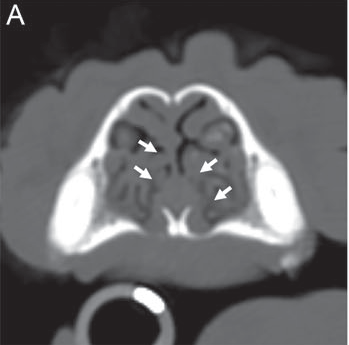

-- diagnosis

Fluoroscopy (or videofluoroscopy), which shows a continuous x-ray image, so that the pharynx can be viewed in motion upon inhaling and exhaling, can confirm pharyngeal collapse. The dog is awake during this procedure, although it may be sedated. Computed tomography (CT) scans can assess structural abnormalities in the pharynx.